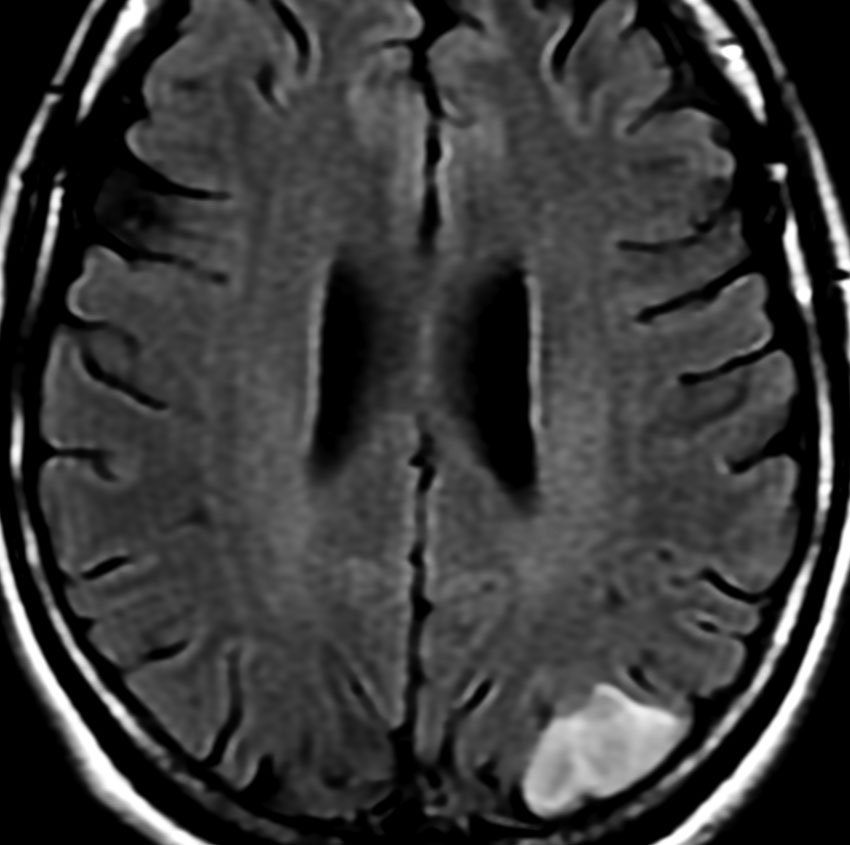

• MRI のT2・FLAIR(フレア)画像で淡く白く見える(高信号)のが特徴です

• 一般的には,びまん性で周囲がはっきりしない脳の中に「にじむような腫瘍」に見えます

• ガドリニウム造影剤で増強されることはほとんどありません

フレア画像です。左上前頭回の星細胞腫ですが,境界がとてもはっきりしていて限局性 localized single gyrus glioma です。びまん性 diffuseには見えません。IDH1の変異があり,1p/19qの欠失はないので星細胞腫グレード2です。上の例とは全く違う臨床像を示しますが,分子病理でも区別はつきません。頑張って早めに全摘出して治してしまった方がいいタイプです。再発を避けるために,supratotal resectionと言って,周囲の正常脳組織も10mmくらい余分に摘出します。